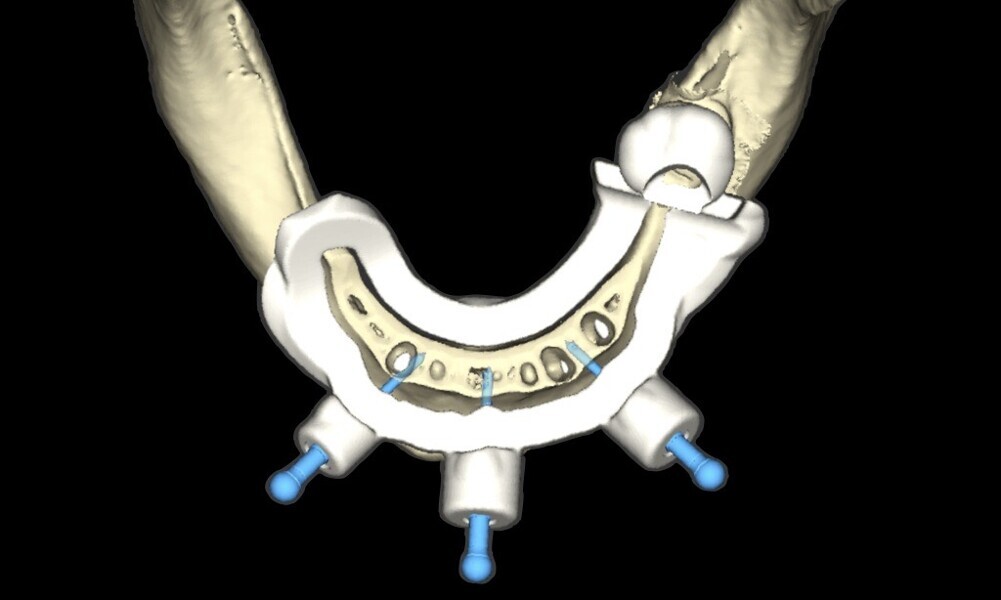

creation of a tooth- and mucosa-supported surgical guide to stabilise the drilling, ensuring accurate 3D positioning of the implants (22–28);

Figs. 16–28: The treatment workflow included the extraction of hopeless teeth, implant planning and positioning, and surgical guide fabrication.